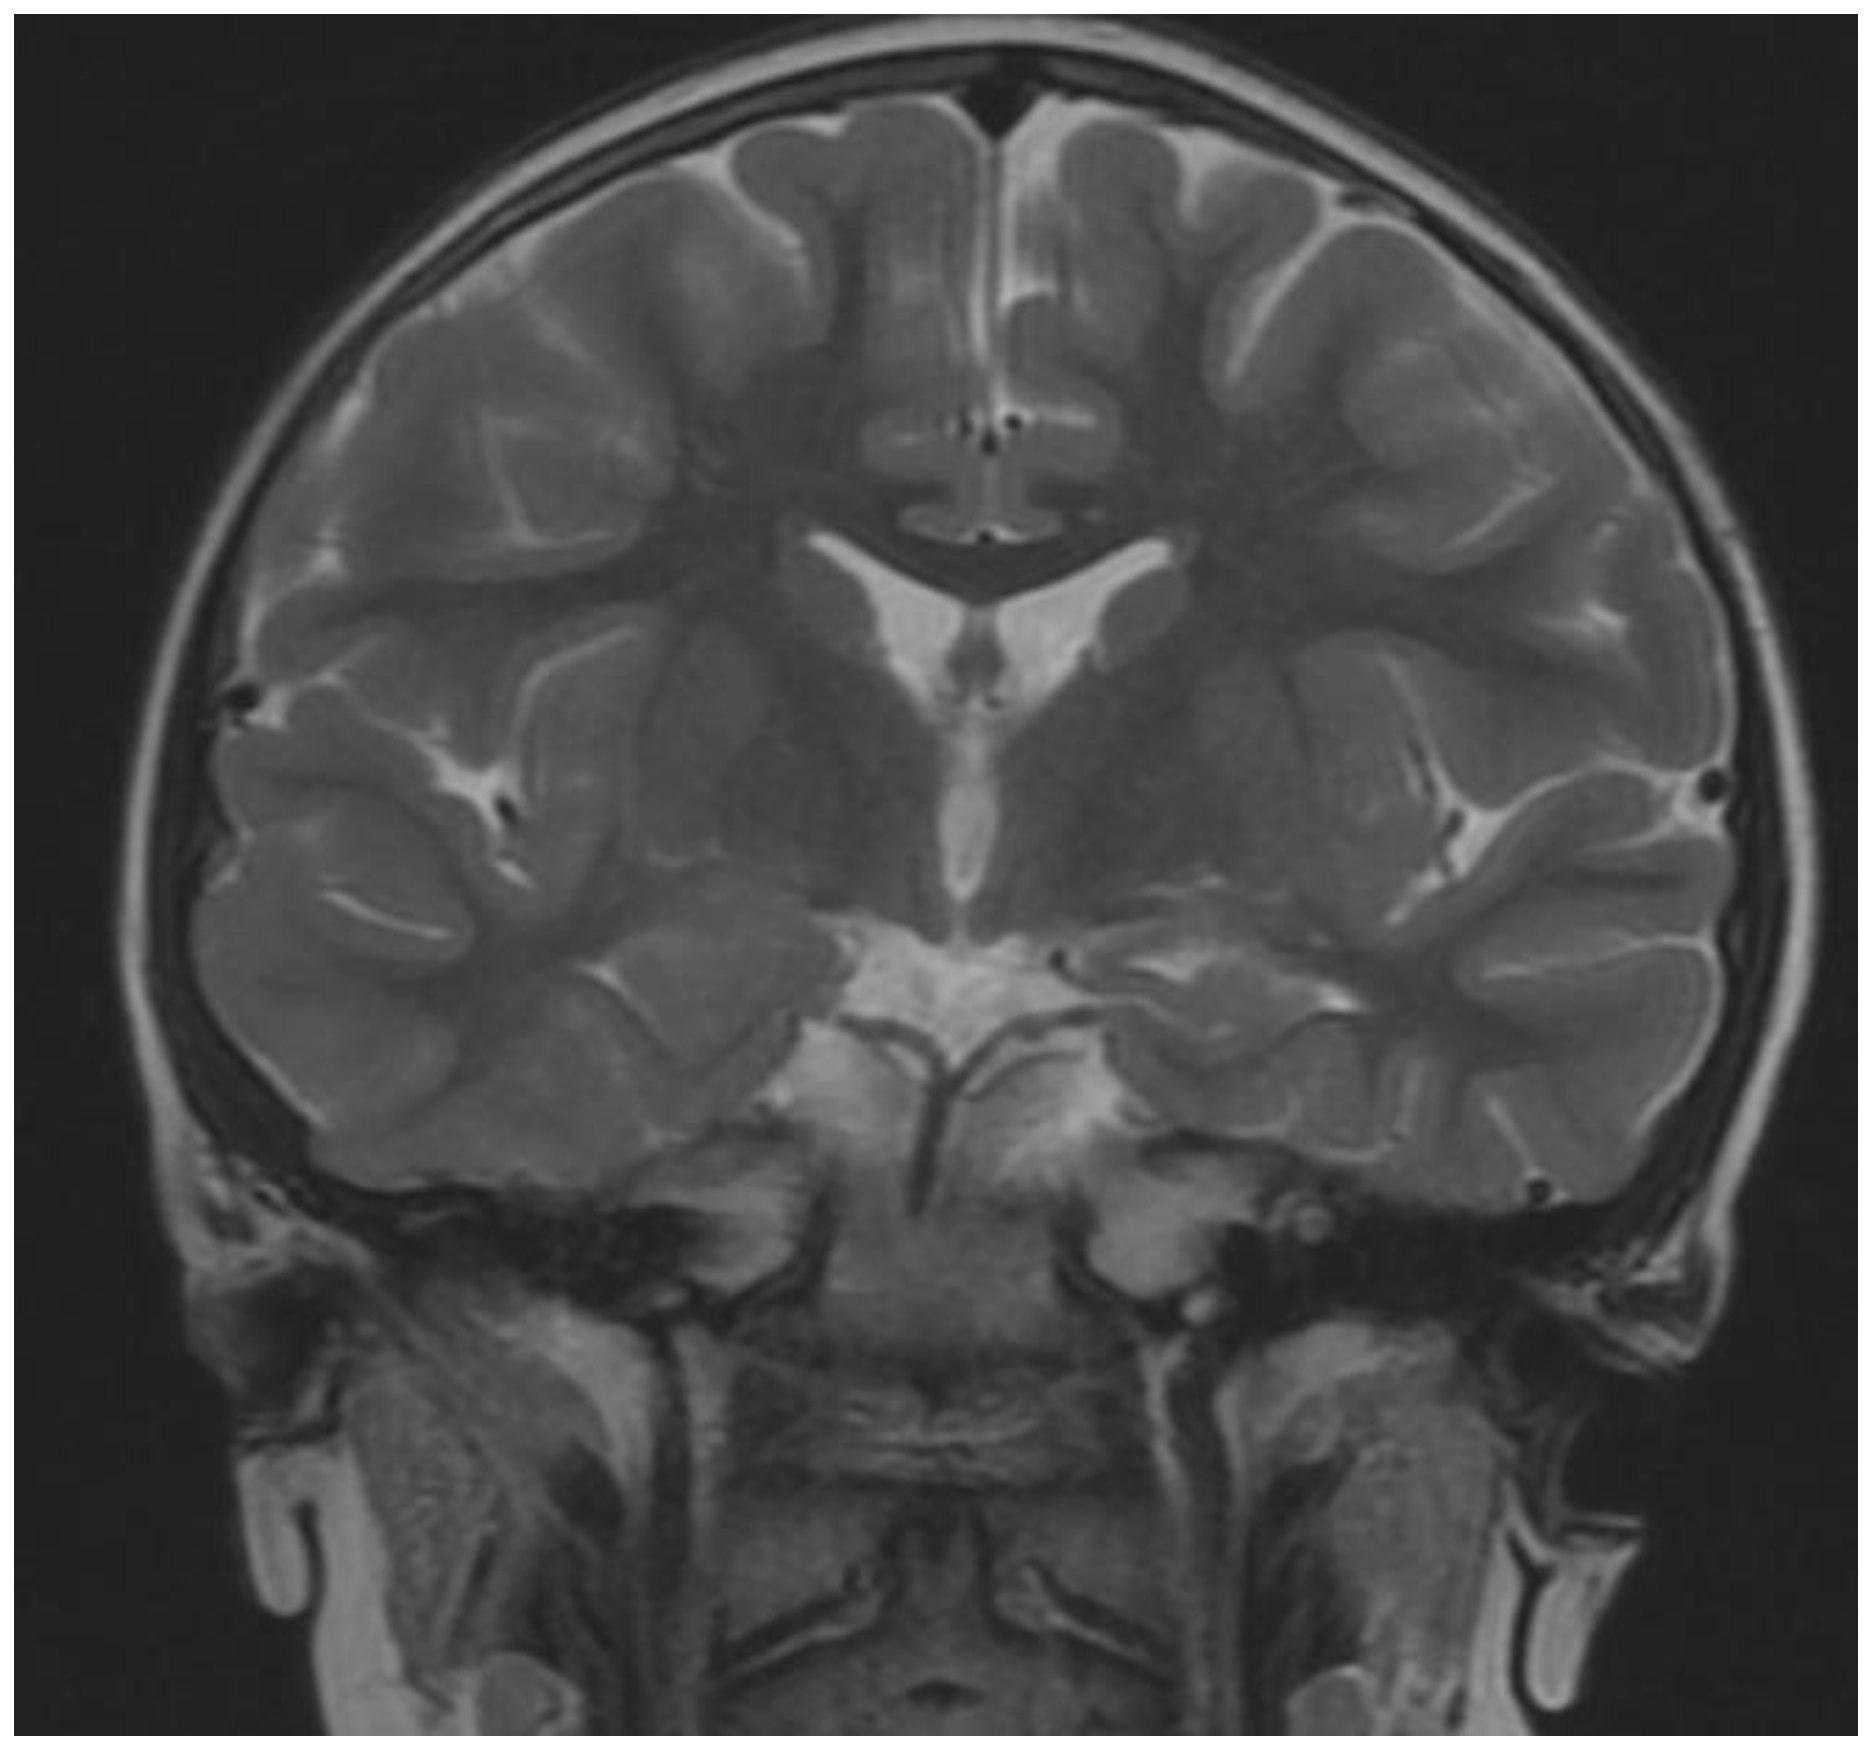

| Brain MRI | |

| no | Polymicrogyria |

| no | Corpus callosum hypoplasia/agenesis |

| no | Ventricular enlargement |

| no | Key-hole shaped temporal horns |

| no | Colpocephaly |

| no | Delayed myelination/decreased cortical white |

| no | Small pons |

| no | Small interior vermis |

| yes | Changes in temporal lobe- cyst |